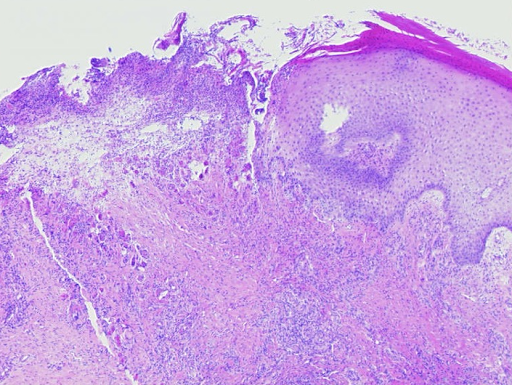

As the granulocytes involved are destroyed as they migrate through the vessel walls, this disease is also known as leukocytoclastic vasculitis (Fig. 3).

Fig. 3: Histological findings of leukocytoclastic vasculitis at a glance, the epidermis is partially destroyed and detached, there is a massive cellular infiltrate of the dermis (a). Segmental granulocytes are found in the vessels and vessel walls. Fibrinoid necrosis of the vessel walls and disintegrating granulocytes, which are also deposited perivascularly (b,c). Residual obstruction and infarction of small cutaneous blood vessels (d,e).